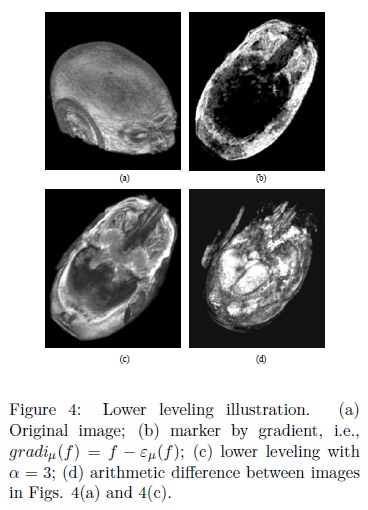

The image in Fig. 4, ilustrates the performance of Eq. 6. In Fig. 4(b) a marker obtained from the internal gradient is shown. The internal gradient is defined as the arithmetic difference between the original image and the eroded one, i.e., gradiμ(f) = f — εμ(f). The internal gradient uniquely detects regions on the skull. The idea of applying Eq. 6 using as marker the internal gradient is to reconstruct precisely the skull. The output image after applying Eq. 6 with α = 3 is displayed in Fig. 4(c). In this image the skull has been separated and reconstructed. Hence the arithmetic difference f —  (f,g), allows us to recover the remaining components, i.e., brain, dura matter, among others, as is illustrated in Fig. 4(d). The problem of separating brain in this way is that the intensity levels of the white matter are similar to the skull bringing as consequence that the marker cannot be obtained uniquely on the bone.

(f,g), allows us to recover the remaining components, i.e., brain, dura matter, among others, as is illustrated in Fig. 4(d). The problem of separating brain in this way is that the intensity levels of the white matter are similar to the skull bringing as consequence that the marker cannot be obtained uniquely on the bone.